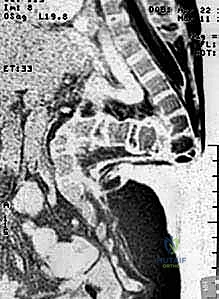

- التصوير الطبي المتقدم: يطلب الدكتور هطيف صور أشعة سينية بانورامية، أشعة مقطعية ثلاثية الأبعاد (3D CT Scan) لفهم التشريح العظمي المشوه، ورنين مغناطيسي (MRI) لتقييم الحبل الشوكي والتأكد من عدم وجود "الحبل الشوكي المربوط" (Tethered Cord).

المرحلة الثانية: الإجراء الجراحي خطوة بخطوة

- التخدير وتجهيز المريض: يتم تخدير الطفل بعناية فائقة، ووضعه على طاولة العمليات بوضعية تحمي الأعضاء الداخلية.

- الشق الجراحي والتعامل مع الأنسجة: يتم فتح الجلد بحذر شديد. في كثير من الأحيان، يتم استئصال الأنسجة الندبية القديمة. يستخدم الدكتور هطيف تقنيات الجراحة المجهرية (Microsurgery) للتعامل مع الأنسجة العصبية الرقيقة وتجنب تسرب السائل النخاعي.

- استئصال الفقرات (The Kyphectomy): هذه هي الخطوة الأكثر حساسية. يقوم الدكتور هطيف بتحديد الفقرات التي تشكل قمة الانحناء (عادة من 1 إلى 3 فقرات). يتم استئصال جسم هذه الفقرات بالكامل مع الأقراص الغضروفية المحيطة بها.

- تصحيح التشوه (Closing the Wedge): بعد إزالة الفقرات، يصبح العمود الفقري مرناً في تلك النقطة. بمهارة فائقة، يقوم الدكتور هطيف بضم الجزأين العلوي والسفلي من العمود الفقري معًا، مما يلغي الانحناء ويستعيد استقامة الظهر.

- التثبيت الميكانيكي (Spinal Fixation): للحفاظ على هذا التصحيح، تُستخدم براغي وأعمدة معدنية مخصصة للأطفال. يتأكد الدكتور هطيف من تثبيت هذه الأدوات بقوة في الحوض والفقرات السليمة لضمان ديمومة النتيجة.

- الترقيع العظمي (Bone Grafting): يتم وضع طعوم عظمية (غالباً من العظام التي تم استئصالها) حول منطقة الجراحة لتحفيز التحام العمود الفقري بيولوجياً لتكوين كتلة عظمية صلبة واحدة.